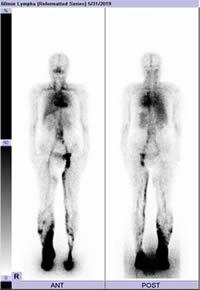

ICGリンパ管蛍光造影検査

ICGリンパ管蛍光造影検査では、近赤外線カメラでリアルタイムにリンパの流れを可視化できるため、診断や治療方針の決定、手術を行う際に有用です(リンパ浮腫検査外来:別項を参照)。

図:ICGリンパ管蛍光造影検査

リンパ浮腫ではリンパ液の皮下への漏出を認める